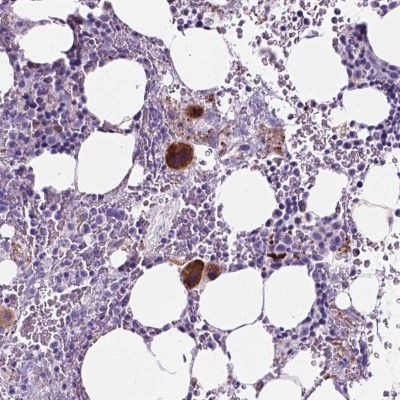

Supportive validation

- Submitted by

- Novus Biologicals (provider)

- Main image

- Experimental details

- Immunohistochemistry: EBLN2 Antibody [NBP2-49572] - Staining of human bone marrow shows cytoplasmic positivity in megakaryocytes.